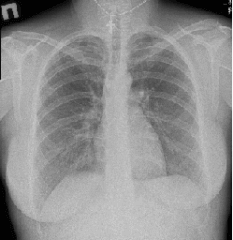

Первый метод, который предложат врачи для обследования позвоночника – рентген. Информативный, быстрый, безболезненный, доступная цена рентгенографии грудного отдела позвоночника – все это применимо к этому методу диагностики. На рентгеновских снимках будут видны строение и особенности позвоночного столба у пациента, искривления и другие деформации, травмы и различные заболевания. Чтобы обследовать состояние определенного отдела позвоночника нет необходимости делать снимок всего позвоночного столба. Лечебно-диагностический центр «Кутузовский» предлагает большой перечень рентгенографических исследований, в том числе и рентген грудного отдела позвоночника. Исследование проводится на современном цифровом рентген-аппарате BrivoXR575Premium, который гарантирует изображение высокого качества, высокую информативность и малую дозу облучения. Процедуру проводят врачи-рентгенологи с опытом работу больше 20 лет – в правильности результата можно не сомневаться!

Несколько секунд, пока делаются снимки, нужно не двигаться. Врач-рентгенолог проанализирует статическую ось грудного отдела позвоночника (замерит углы кифоза и сколиоза), форму и структуру тел позвонков, ножки дуги, остистые, поперечные и суставные отростки, высоту тел позвонков, межпозвонковых дисков, наличие костных разрастаний на телах позвонков. Видимые отделы ребер, форму реберно-поперечных и реберно-позвоночных суставов. Паравертебральные мягкие ткани.

На рентгенограмме грудного отдела позвоночника врач-рентгенолог видит и оценивает:

- состояние тел позвонков – в норме не должно быть трещин, смещений, изменения высоты между позвонками, изменений формы тел

- патологии (есть или нет) в межпозвоночных дисках

- места прикрепления рёбер к позвонкам

- форму позвоночного столба